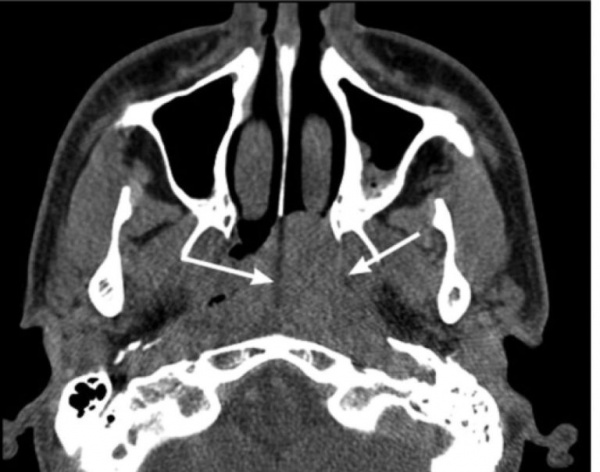

Подросток, 14 лет, обратился в клинику с жалобами на длительную двустороннюю заложенность носа и систематические носовые кровотечения. Возникновение симптомов впервые отметил 12 мес назад, обращался к врачу-оториноларингологу по месту жительства, получал лечение по поводу хронического риносинусита, без положительной динамики. При обращении в ФГБУ «НМИЦ ДГОИ им. Дмитрия Рогачева» была выполнена эндоскопия носа с визуализацией новообразования, обтурирующего полость носа и хоану справа. При выполнении МСКТ околоносовых пазух выявлено сосудистое новообразование полости носа, носоглотки и околоносовых пазух с патогномоничными рентгенологическими признаками ЮАН. В соответствии с классификацией Fisch-Andrews данная ЮАН стадирована как IIIa: опухоль заполняет клиновидную пазуху, носоглотку, распространяется в крыловидно-небную ямку, далее через нижнюю глазничную щель в полость орбиты; опухоль разрушает большое крыло клиновидной кости и крыловидный отросток, распространяясь в закрыловидное пространство. МСКТ околоносовых пазух также позволила визуализировать правую ВВА, которая проходила непосредственно за задней стенкой верхнечелюстной пазухи (см. рисунок). Данное положение ВВА позволяет выполнить ее трансназальное клипирование. Учитывая этот факт, нами было принято решение удалить ЮАН без предварительной эмболизации. Операция проводилась под общей анестезией, в условиях управляемой гипотонии. С целью хирургического доступа была выполнена модифицированная эндоскопическая медиальная максиллэктомия по Денкеру и этмоидотомия справа. Трансназальный модифицированный эндоскопический доступ по Денкеру включает в себя удаление медиальной стенки верхнечелюстной пазухи и расширение грушевидной апертуры латерально, что позволяет получить широкий хирургический коридор, достаточный для манипуляций в области подвисочной ямки [10]. Для обеспечения адекватной широты хирургического пространства и мобилизации опухоли была произведена двусторонняя сфенотомия с резекцией рострума и перегородки клиновидной пазухи. Затем задняя стенка верхнечелюстной пазухи была резецирована, выполнена экспозиция содержимого подвисочной ямки путем рассечения ее периоста серповидным скальпелем. После бережного выделения ВВА было выполнено, используя клипаппликатор, наложение двух титановых клипс на ее основной ствол. Далее компонент опухоли в крыловидно-небной ямке был отсепарован от здоровых тканей, мобилизован компонент из полости орбиты. Дальнейшая диссекция опухоли, в частности резекция крыловидного отростка, вызвала кровотечение за счет дополнительного кровоснабжения опухоли из бассейна внутренней сонной артерии через видиеву артерию. Кровотечение остановлено биполярной коагуляцией. Несмотря на выполненные методы контроля гемостаза, во время операции отмечалось умеренное кровотечение, не затрудняющее удаление опухоли. После мобилизации всех компонентов опухоли ЮАН была низведена в ротоглотку и удалена трансорально. Послеоперационная полость заполнена пеной на основе карбометилцеллюлозы. Операционная кровопотеря составила 1100 мл и не потребовала гемотрансфузий. На следующие сутки после хирургического вмешательства пациенту была выполнена МСКТ с внутривенным контрастированием, которая не выявила признаков резидуальной опухолевой ткани. Стандарты лечения ЮАН в нашем отделении предполагают выполнение контрольной МСКТ с внутривенным контрастированием на 1—2-е сутки после операции для определения радикальности проведенной операции; в случае если по данным МСКТ визуализируется резидуальная опухолевая ткань, пациенту выполняется ревизионная операция с удалением остаточного компонента.

Рис.. МСКТ головы с контрастным усилением до и на вторые сутки после операции.